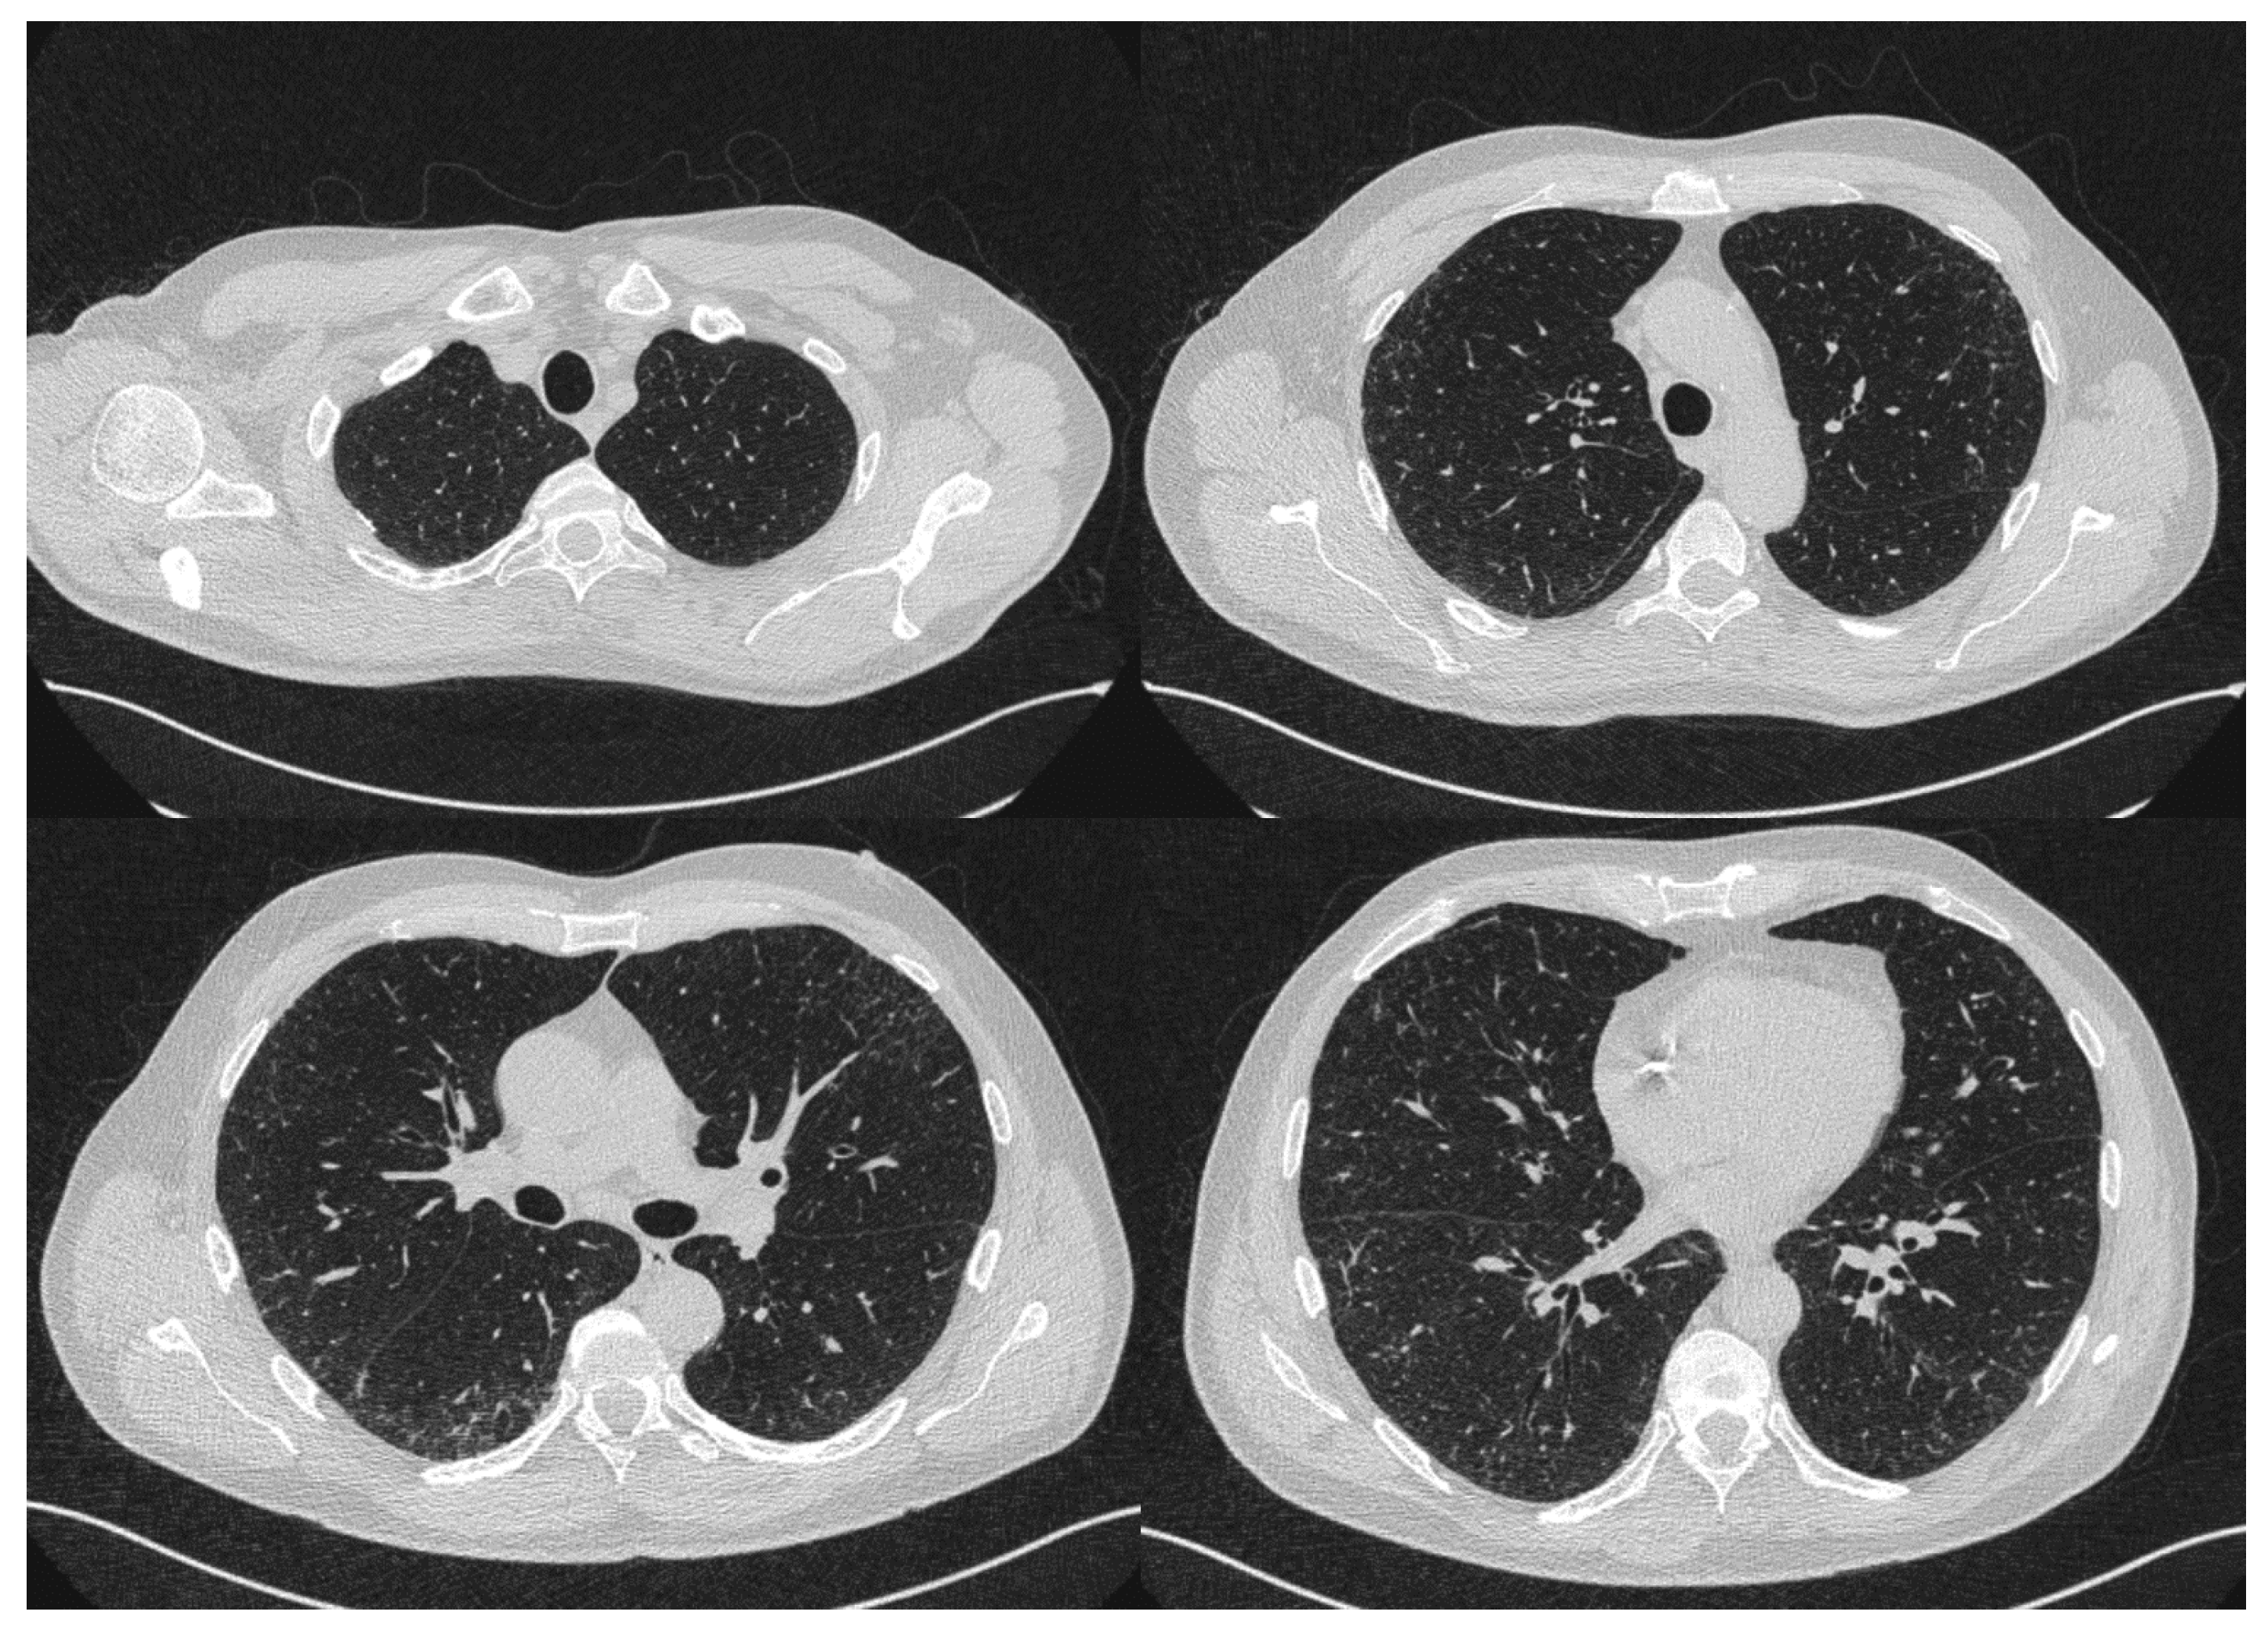

2. Case Report